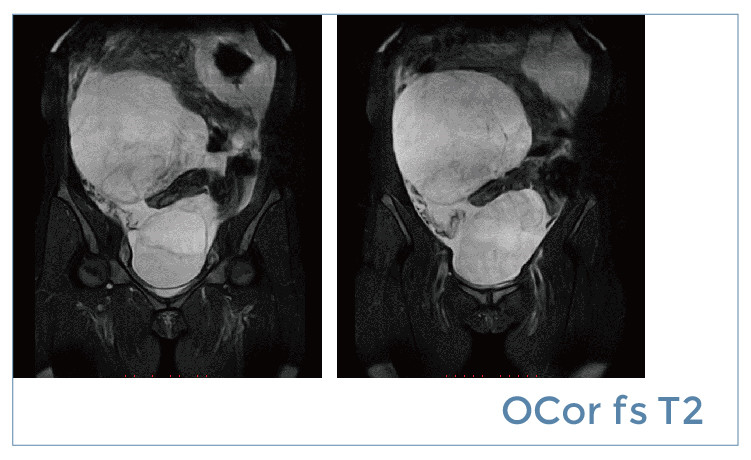

【朗润影像档案】磁共振影像病例分享(编号20190419)